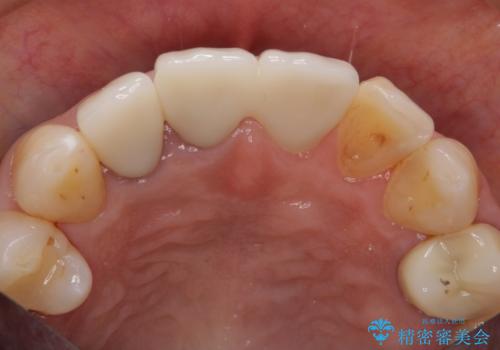

前歯のすき間 以前よりも広がってきた 二度と広がらないようにしたい セラミック治療

- 前歯のすき間を気にして来院。

右上2本を以前セラミックにしたが、前歯のすき間が広がってきてしまったとのこと。

右上の前歯のみの被せなおしですと、右上の前歯が反対側に比べて極端に大きくなってしまうことを説明し、左上の前歯も併せてセラミックにすることにしました。

右上の前歯二本、左上の前歯1本をセラミックにし、正中の前歯を2本連結しました。

連結しなくても、ナイトガード使用で防止できると説明しましたが、手間をかけずに二度と広がらない方がいいとのことで連結を強くご希望でした。

また、見た目の歯と歯の分離感も、連結しない方が表現することが可能です。

気になっていたすき間が閉じて、大変喜んでいただけました。